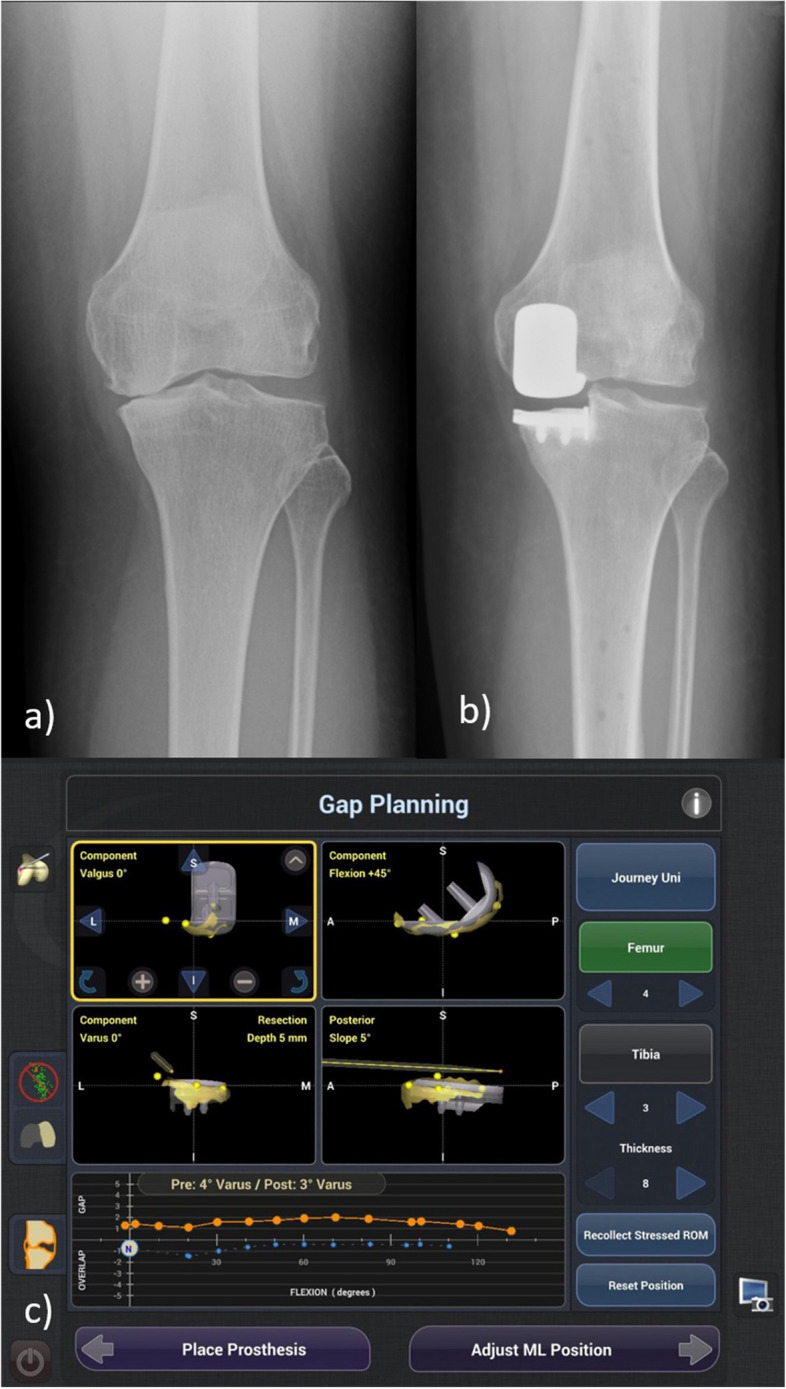

Background: Survivorship of medial unicompartmental knee arthroplasty (UKA) is technique-dependent. Correct femoral-tibial component positioning associates with improved survivorship. Image-free robotic-assisted unicompartmental knee arthroplasty enables preoperative and intraoperative planning of alignment and assessment of positioning prior to execution. This study aimed to compare the radiological outcomes between robotic-assisted UKA (R-UKA) and conventional UKA (C-UKA).

Methods: This retrospective case control study involved 140 UKA (82 C-UKA and 58 R-UKA) performed at an academic institution between March 2016 to November 2020, with a mean follow-up of 3 years. Postoperative radiographs were evaluated for mechanical axis and femoral-tibial component position. Component position was measured by two methods: (1) femoral-tibial component contact point with reference to four medial-to-lateral quadrants of the tibial tray and (2) femoral-tibial component contact point deviation from the center of the tibial tray as a percentage of the tibial tray width. Baseline demographics and complications were recorded.